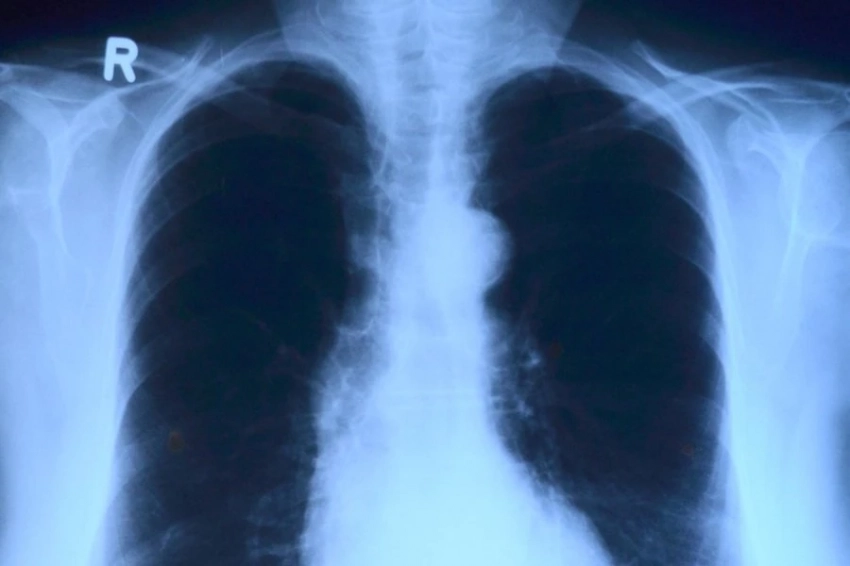

В рамках проводимых экспериментов на лабораторных грызунах, ученые имплантировали им клетки рака легкого человека и проводили тестирование в трех различных вариантах введения астанина-211: в кровь, прямо в опухоль, или с зондом. Так, при использовании зонда с радионуклидом, опухоли распространялись примерно в три раза меньше, а при введении астанина-211 в кровь выживаемость подопытных составила 80%. Наилучший же результат показал метод введения вещества непосредственно в опухоль, при котором выживаемость составила все 100%.